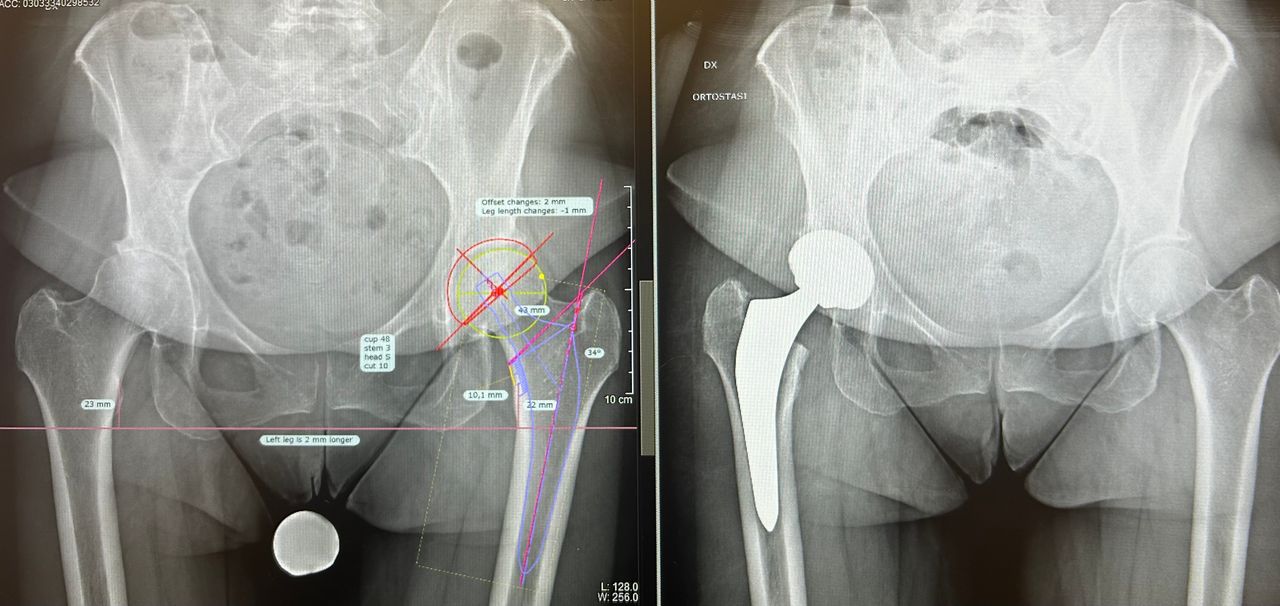

Mi chiamo Luca Luciano e sono un medico ortopedico specializzato nella chirurgia protesica dell’anca e del ginocchio. Da anni mi occupo del trattamento dell’artrosi severa, utilizzando tecniche mini invasive moderne che mi permettono di ridurre il dolore post-operatorio e favorire un recupero più rapido e sereno.

Credo in una chirurgia precisa, attenta e rispettosa dei tessuti. Ogni intervento viene pianificato con cura, valutando la storia clinica, le esigenze e lo stile di vita della persona che ho di fronte. Il mio obiettivo non è solo sostituire un’articolazione consumata, ma restituire qualità di vita, autonomia e sicurezza nei movimenti quotidiani.

Il dottore Luciano è un ortopedico in cui si coniugano perfettamente professionalità, umanità e grande attenzione, merce rara! Ho effettuato protesi completa di anca e femore in chirurgia miniinvasiva.

Intervento riuscitissimo(e il mio era un caso piuttosto complesso!), ho camminato bene dai primi giorni, il dottore, con eccesso di scrupolo, ha seguito il decorso e le medicazione fino alla completa guarigione, sempre reperibile per qualsiasi imprevisto. Immensamente grata.

Il Dottor Luca Luciano si è dimostrato un professionista di grande competenza e umanità. Fin dal primo incontro ha saputo spiegare con chiarezza ogni dettaglio dell’intervento all’anca, rassicurandomi e facendomi sentire sempre seguito.

Nonostante il mio fosse un caso complesso, ha affrontato la situazione con sicurezza e determinazione, proponendo un intervento di protesi d’anca con tecnica mini-invasiva. Il decorso è stato sorprendentemente rapido e il risultato finale eccellente.